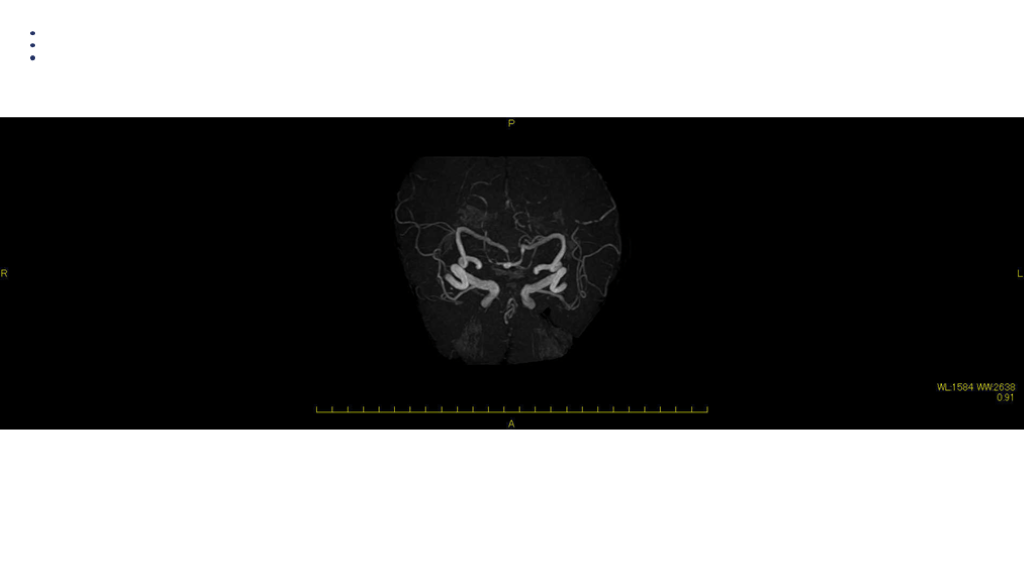

画像 所見

画像 所見 FLAIR DWI